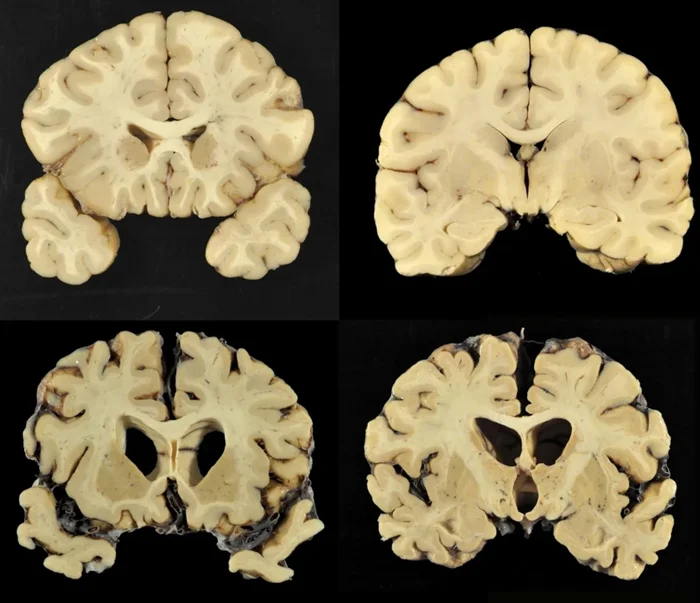

Действительно, как показало вскрытие, Крис Бенуа долгое время страдал из-за множества нелеченых сотрясений головного мозга. Эксперт, проводивший исследование, отмечал тот факт, что мозг Бенуа был так сильно повреждён, что напоминал мозг 85-летнего больного болезнью Альцгеймера, а ещё одно сотрясение мозга могло привести к тяжёлой деменции и вытекающим из этого серьёзным поведенческим проблемам. Всё это говорит о том, что спортсмен страдал от ХТЭ. Но неужели раньше об этом заболевании никто не слышал?

Сравнение мозга здорового человека и мозга спортсмена с ХТЭ